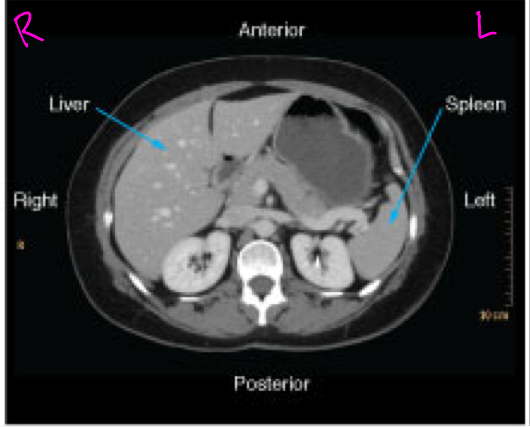

Axial CT images

Presented as if the viewer is standing at the foot of the patient’s bed; the patient’s right is to the viewer’s left; the anterior aspect of the patient is toward the top of the image

Abdominal and pelvic CT

Evaluating the abdominal organs for pathology such as acute abdomen or trauma